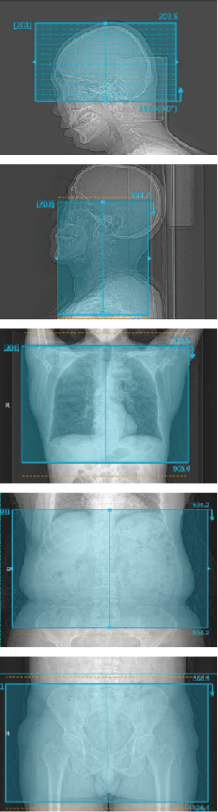

自动精准识别扫描部位: 头、颈、胸、腹、盆

智能扫描范围